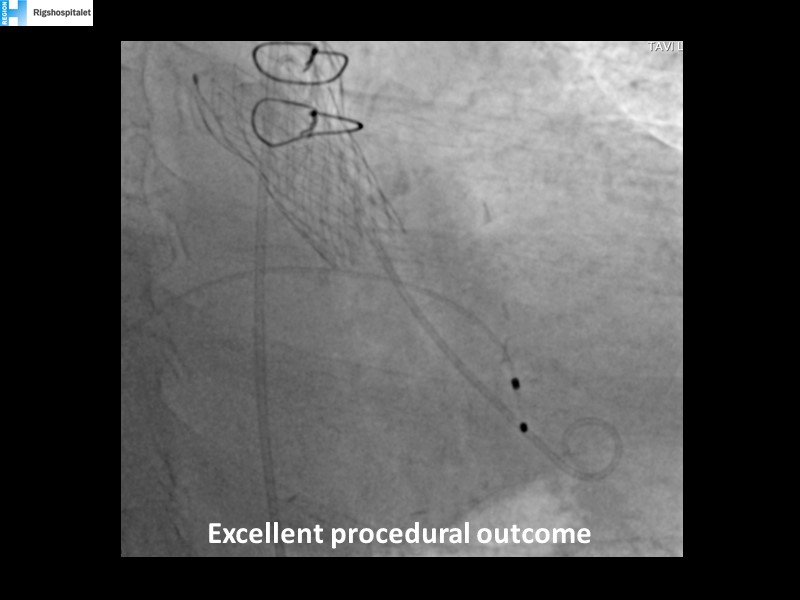

Your most challenging TAVI cases - Achieving precision and control with Evolut platform

How to deal with challenging anatomies? Find answers in this EuroPCR 2022 session with case studies to explore and learn how to achieve optimal patient outcomes with Evolut platform, uncover practical tips and techniques to achieve implant precision and control, and become familiar with technical considerations and procedural execution of TAVI.